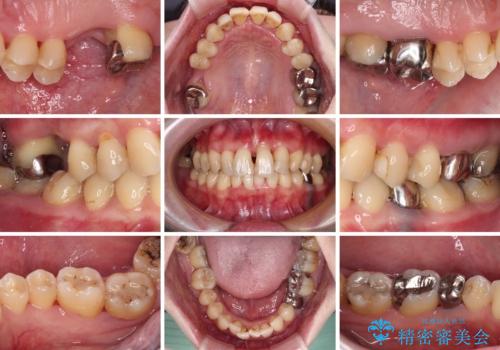

- かかりつけ医にて歯周病治療の名目で治療を行っていたものの、治療プランが明確でないままにインプラント処置を行うとことに疑問を感じ、来院された患者様です。

かかりつけ医では、歯周病治療は終了したため、抜歯を行った右上奥歯にインプラント埋入を行うとの案内があったそうです。

検査を行ったところ、歯周外科処置や抜歯が必要と思われる箇所が散見されたため、あらためて当院に歯周病の初期治療から行うこととしました。

下顎前歯の叢生も気になっており、矯正治療も並行して進めていくこととしました。

自他共に認める、非常に色白の患者様であったため、黄ばんだ歯の色を白くすることを希望されており、歯周病治療の該当部位に限らず、全顎的にオールセラミッククラウンにて補綴治療を行うこととしました。